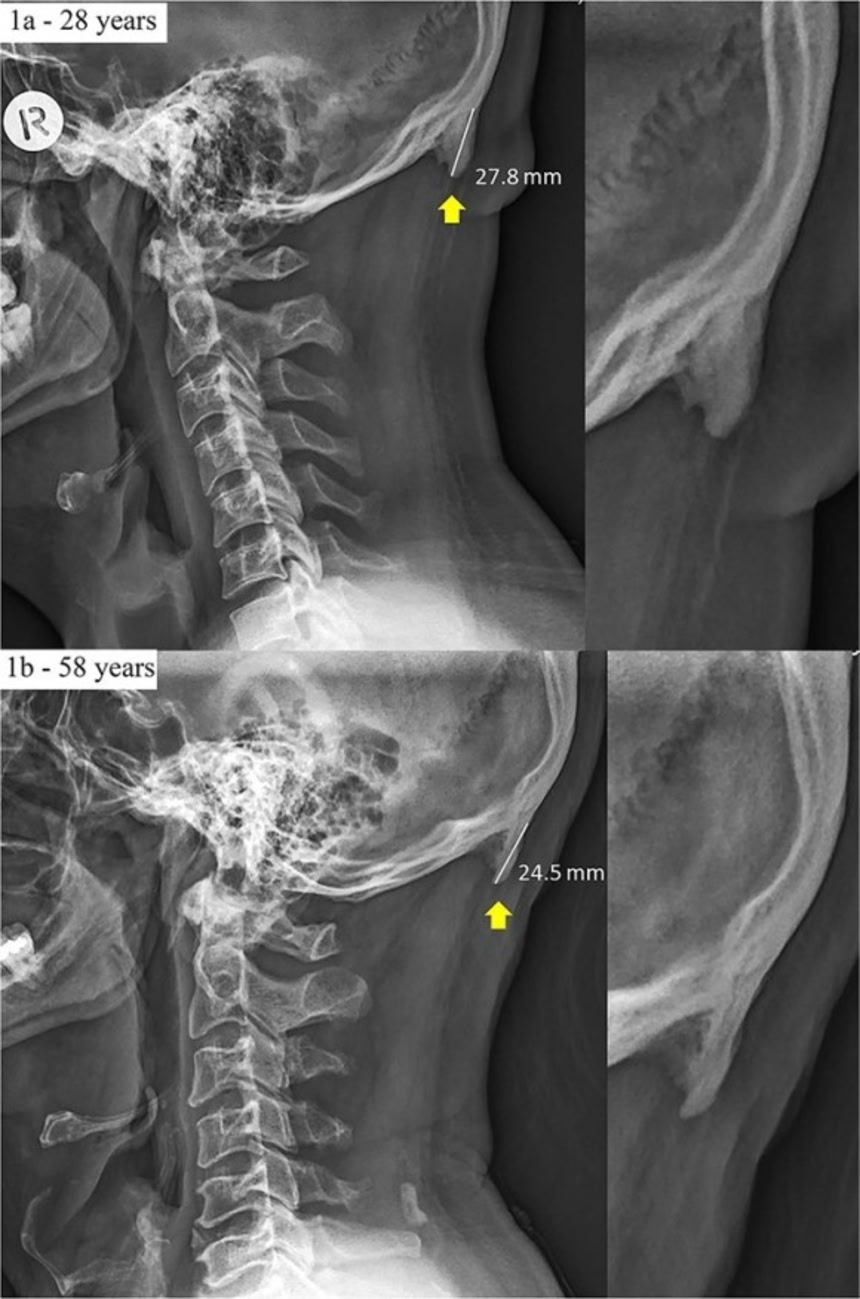

そもそもシャハール氏らの研究はツノについてのものではない。ワシントンポストの記事で”ツノ”や”ツノ状の突起”と呼ばれているものは、小さな骨棘の一種のことで、頭蓋骨の両脇から生えるものではなく、後頭部の下の部分に生じる。

そこは「外後頭隆起」という部分だ。ここには脊椎がつながっている部分に沿って重要な靭帯と筋肉がある。自分自身の後頭部を触ってみれば、硬い塊があるのがわかるだろう。そこが外後頭隆起だ。

これが骨棘の一種である骨の突起だ。研究では、これのことを「伸長した外後頭隆起」と呼んでいる。

研究では、カイロプラクティックに通う18~86歳の患者1200人のかつて撮られたレントゲン写真を引っ張り出して、60歳以上の25パーセントに骨棘があることを発見した。それまでずっと筋肉が使われてきたことを考えれば、特に驚くには当たらないだろう。

注目されたのは18~30歳のグループだ。60歳よりも若いグループになると外後頭隆起が生じている割合が減っていたのだが、その若年グループに限っては40パーセントに外後頭隆起が見られたという。